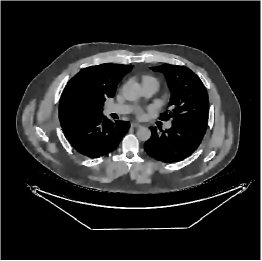

This section compares the reconstruction quality and runtime among the proposed MBIR method, PWLS-ST-, and other three MBIR methods, PWLS-EP, PWLS-DL, and PWLS-ST-. Table I shows that, for both 2D and 3D sparse-view CT reconstructions of the XCAT phantom, the proposed PWLS-ST- model outperforms PWLS-EP and PWLS-ST- in terms of RMSE. In addition, PWLS-ST- using a square transform (of size ) achieves lower RMSE than PWLS-DL using an overcomplete dictionary (of size ) for 2D sparse-view reconstructions. Fig. 3(a) and Fig. 4 show the reconstructed images for 2D and 3D phantom experiments, with different reconstruction models and different number of views. (See the corresponding error maps in the supplement.) The proposed PWLS-ST- consistently gives more accurate image reconstructions compared to other MBIR methods. Specifically, PWLS-ST- has smaller errors in the heart region (see zoom-ins in Fig. 3(a)) of 2D reconstructions than PWLS-DL and PWLS-ST-. In addition, compared to PWLS-ST-, PWLS-DL and PWLS-ST- have some ringing artifacts around the edges with high transition, e.g., edges between air and soft tissues. (See a comparison of profiles of PWLS-ST- and PWLS-ST- in the supplement.) In particular, PWLS-ST- and PWLS-DL give more visible ringing artifacts for 2D reconstruction from fewer views, and PWLS-ST- has these ringing artifacts for 3D reconstructions regardless of the number of views (see zoom-ins in Fig. 4). Table II reports runtimes of different MBIR methods in reconstructing the -views XCAT phantom scan. (FBPConvNet is a non-MBIR method and its runtime for processing a image is approximately one second with a TITAN Xp GPU.) While providing better reconstruction quality, the proposed Algorithm 1 of PWLS-ST- has shorter runtime compared to the algorithms of PWLS-DL and PWLS-ST- in Section III-A. Similar to the PWLS-EP algorithm, the reconstruction time of the PWLS-DL, PWLS-ST-, and PWLS-ST- algorithms can be further reduced by using ordered subsets [51].

Fig. 3(b) shows that when tested on the clinical scan data, the proposed PWLS-ST- method improves reconstruction quality in terms of noise and artifacts removal (e.g., see zoom-ins for soft-issue regions), and edge preservation (e.g., see zoom-ins for bone regions), compared to PWLS-EP and PWLS-ST-. Compared to PWLS-DL, PWLS-ST- achieves comparable image quality, but requires less computational complexity.

The benefit of the proposed PWLS-ST- over PWLS-ST- can be explained when there exist some outliers for some : in (12) gives equal emphasis to all sparse codes – from small to large coefficients that generally correspond to edges in low- and high-contrast regions, respectively – in estimating ; however, PWLS-ST- adjusts to mainly minimize the outliers, i.e., it may not pay enough attention to reconstruct regions with small coefficients. The histogram results in Fig. 1 reveal model mismatch of PWLS-ST- over the iterations. Fig. 3, Fig. 4, and Table I show that PWLS-ST- can moderate model mismatch, and provides more accurate reconstruction than PWLS-ST-.